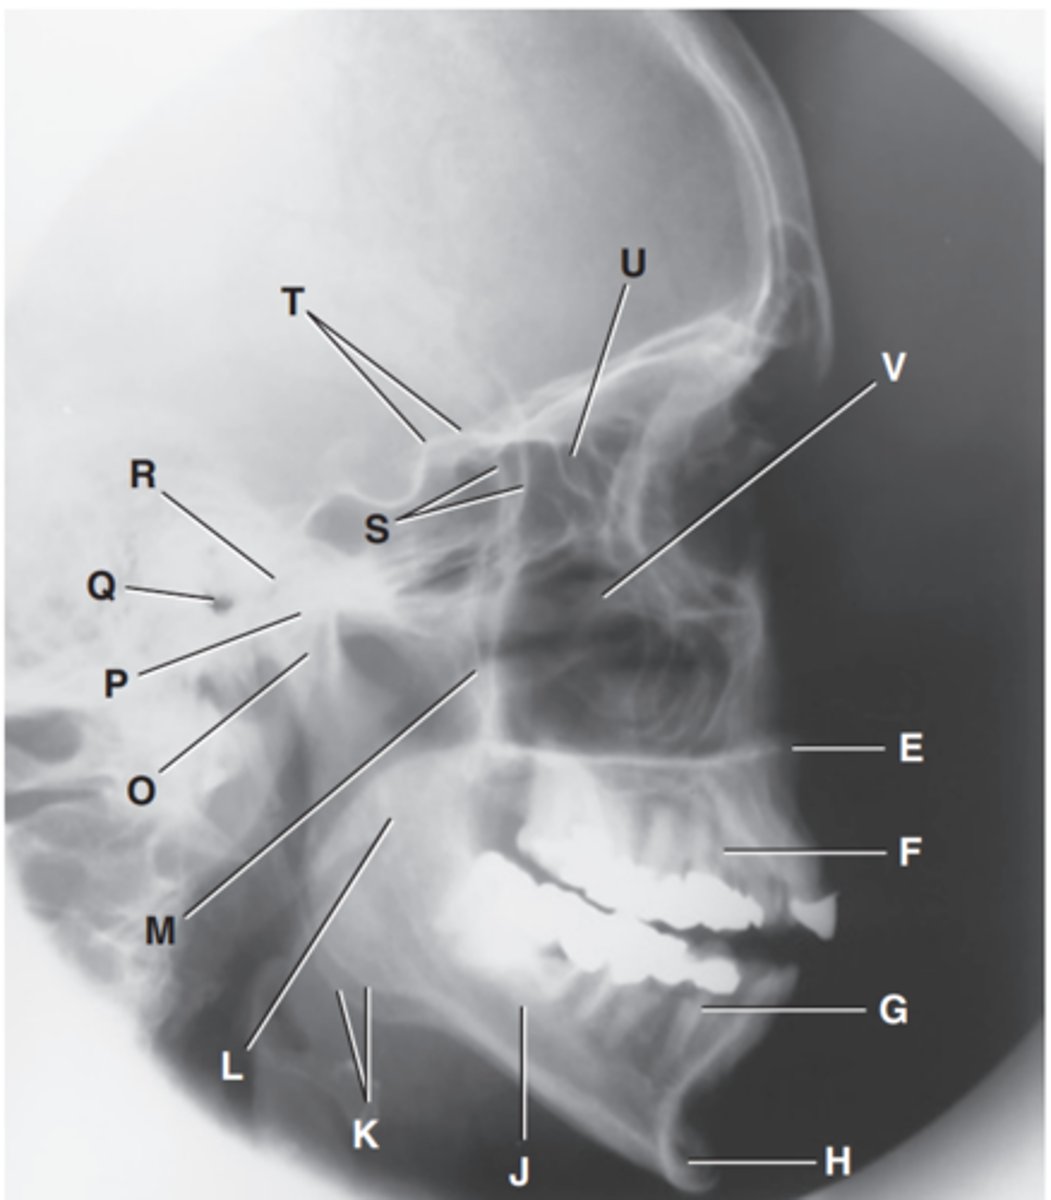

Zygomatic arch

Label A

Right zygomatic bone

Label B

Right nasal bone

Label C

Frontal process of right maxilla

Label D

Anterior nasal spine

Label E

Alveolar process of maxilla

Label F

Alveolar process of mandible

Label G

Mentum or mental protuberance

Label H

Mental foramen

Label I

Body of mandible

Label J

Angle (gonion)

Label K

Ramus of mandible

Label L

Coronoid process

Label M

Mandibular notch

Label N

Neck of mandibular condyle

Label o

Condyle or head of mandible

Label P

EAM

Label Q

TM fossa of temporal bone

Label R

Greater wings of sphenoid

Label S

Lesser wings of sphenoid with anterior clinoid processes

Label T

Ethmoid sinuses between orbits

Label U

Body of maxilla containing maxillary sunuses

Label V